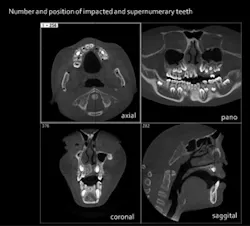

- Locating supernumerary teeth — CBCT images show the positions of supernumerary teeth and provide the means to determine an accurate relationship between the extra teeth and the structures surrounding them.